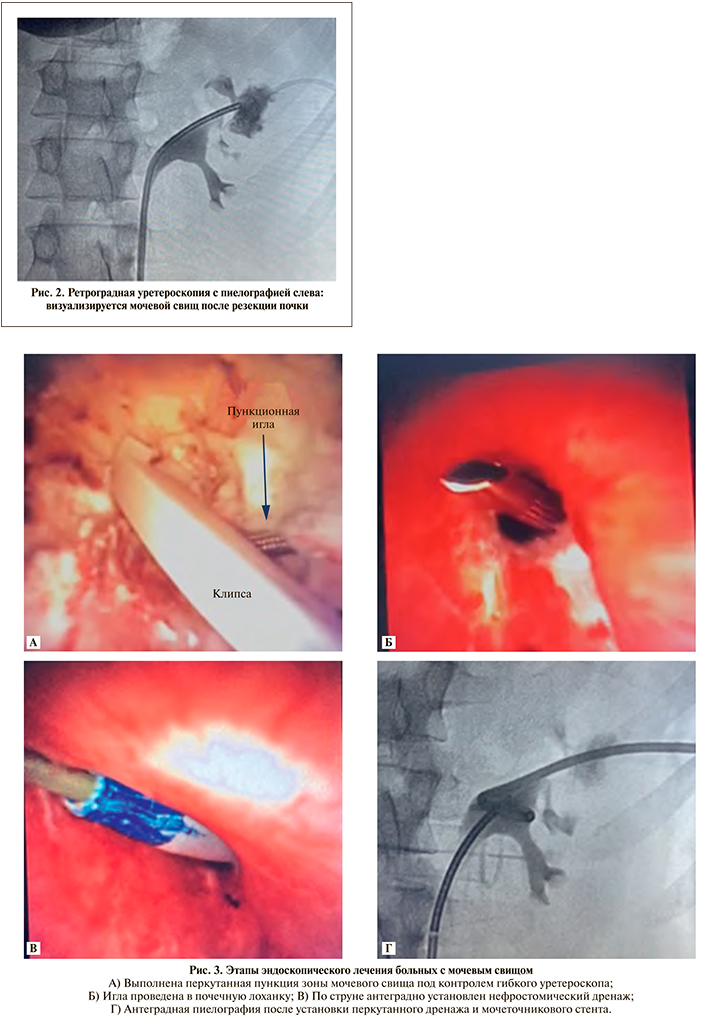

Все вмешательства выполнялись в эндоурологической операционной. Пациентов укладывали в Galdakaoмодифицированное положение Valdivia на спине для выполнения симультанных ретрои антеградных вмешательств на ВМП (рис. 1). Вначале выполнялась диагностическая цистоскопия, оценивалось состояние стенок мочевого пузыря и устьев обоих мочеточников. При наличии стента его извлекали и в мочеточник устанавливали гидрофильный проводник. Далее выполнялась уретеропиелоскопия ригидным эндоскопом 8,5 Ch и при обнаружении небольшого камня лоханки смещали его в верхнюю чашечку, где и проводилась лазерная контактная литотрипсия без установки мочеточникового кожуха. Подобное вмешательство выполнено у 12 (11,3%) из 106 больных. Пункция ЧЛС почки под ультразвуковым наведением и бужирование перкутанного доступа под контролем ригидного уретероскопа проводились в 4 (3,8%) случаях. В отношении остальных 90 (84,9%) пациентов использовались гибкий уретероскоп Storz или одноразовые эндоскопы Boston Scientific. После удаления стента по проводнику до почки устанавливался мочеточниковый кожух 12 Fr, через который в полостную систему почки заводился гибкий уретероскоп. При наличии солитарного камня лоханки или нижней чашечки выполнялось контактное лазерное дробление, фрагменты извлекались с помощью петли Дормиа 2,4 Fr или путем техники «попкорна» измельчались до пыли. У 18 (17,0%) больных с множественными камнями формировался ретроградно эндоскопически контролируемый перкутанный доступ, через который удалялась основная часть камня. Далее гибким уретероскопом выполнялась ревизия всех чашечек почки, обнаруженные камни смещались в лоханку и извлекались наружу по кожуху Amplatz. При дивертикулах чашечки вначале лазером рассекали и расширяли их шейку, далее выполняли литотрипсию и фульгурацию слизистой. К симультанному перкутанному доступу в отношении них не прибегали. При наличии солитарной опухоли почечной лоханки после уретеропиелоскопии выполнялась резекция образования и фульгурация его основания. Пяти пациентам с МС после резекции почки по поводу опухоли проведено его закрытие по предложенной нами методике [16]. Вначале выполняли уретеропиелоскопию с ретроградной пиелографией, обнаруживали поврежденную чашечку (рис. 2). Далее под комбинированным ультразвуковым и рентгенологическим контролем производили прицельную пункцию травмированной чашечки, ориентиром при этом служил дистальный конец гибкого эндоскопа. После появления в свищевом ходе вне почки кончика пункционной иглы под визуальным контролем проводили ее дальше через поврежденную чашечку в лоханку. Далее устанавливали струну, бужировали пункционный ход, устанавливали нефростомический дренаж и мочеточниковый стент. Этапы операции приведены на рис. 3. В дальнейшем вокруг нефростомического дренажа формировался прямой устойчивый свищевой ход. Стент извлекали через 4–6 нед,, выполняли антеградную пиелографию, при адекватной проходимости ВМП нефростомический дренаж удаляли.

Операции по поводу МС после резекции почки также были успешными. Осложнений мы не наблюдали. Время операции в среднем составило 45,0±20,5 мин (40–65 мин). После удаления нефростомического дренажа только у двоих больных в течение одного дня наблюдалось отделяемое по свищу, которое самостоятельно прекратилось. У трех пациентов свищ зажил сразу. Эффективность лечения за период наблюдения 24±8 (12–30) мес. составила 100%.